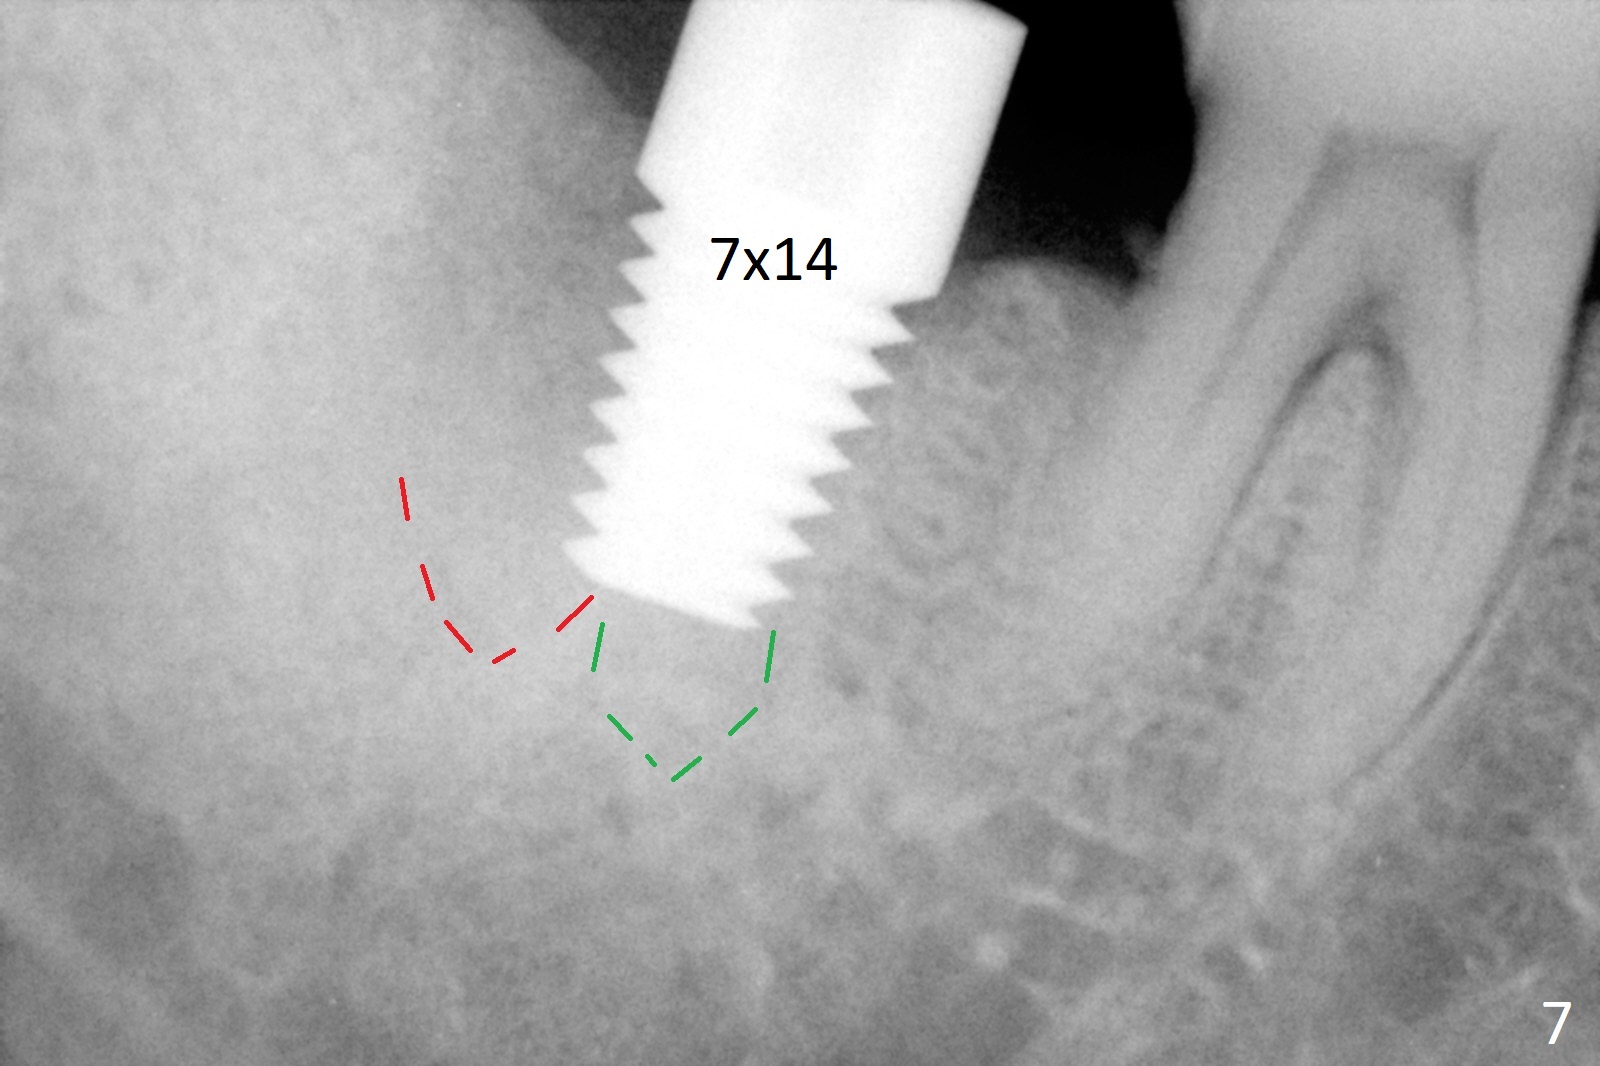

A 50-year-old man, a smoker, presents to clinic with pain of the tooth #15 with apparently occlusal trauma (Fig.1). Two years and three months after #15 extraction, he returns for #31 extraction (Fig.2) and socket preservation (Fig.3). The socket depth is 17 mm along the long axis of the socket 2.5 months post extraction (Fig.4, gingival level). Initial osteotomy is created in the mesial slope of the socket for 14 mm (Fig.5). After sequential osteotomy, a 6x17 mm tap is seated shallower (Fig.6) than the 2 mm drill (Fig.5). Following further osteotomy, a 7x14 mm implant is seated incompletely (Fig.7), which was not found intraop. The implant becomes loose with purulent discharge 19 days postop. The patient returns for 2nd placement 2 months post implant removal (Fig.8). Osteotomy is created probably in the mesial slope with 17 mm (bone level, Fig.9). After insertion of 5 (Fig.10) and 6 (Fig.11) x20 mm taps (tissue level), a 6x20 mm tissue-level implant is placed with clearance from the Inferior Alveolar Canal (Fig.12 yellow dashed line). The implant is restored 8.5 months postop (Fig.13) without bonding 5 mm 0 degree unipost. The crown dislodges 4 months post permanent cementation. Still the patient complains of small crown without occlusal contact. Impression is taken for a new normal-sized crown. The new crown becomes loose 1 year 9 months post cementation (Fig.14). The teeth #14 and 15 remain unrestored.